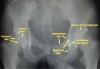

1) Pelvic AP : 6 cardinal lines가 중요

① Iliopectineal line(=Iliopubic line)

② Ilioischial line

③ Tear drop : Femoral head와의 거리가 11mm 이상이거나 양측의 차이가 2mm 이상일 때 비정상

④ Acetabular roof

⑤ Anterior border

⑥ Posterior border